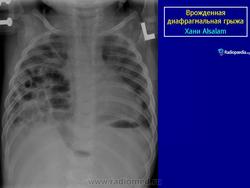

Врожденная диафрагмальиая грыжа встречается с частотой 1 на 2000 рождений. Многие из детей с ВДГ и многоводием у матери умирают после рождения, так как желудок пролабирует в грудную полость и имеет место значительное недоразвитие легкого. После рождения у ребенка возникают трудности в прохождении воздуха в легкие, так как нет сокращения диафрагмы и, кроме того, сдавление усугубляется гиперпневмотозом кишечника. Наблюдается цианоз, гипоксия, алкалоз. У таких детей уменьшен живот в размерах (ладьевидный живот), некоторая асимметрия грудной клетки, смещение тонов сердца, отсутствие дыхания на стороне грыжи.

Диагноз может быть установлен пренатально при ультразвуковом исследовании, после рождения при рентгенологическом. По литературным данным, от 5 до 25% диафрагмальных грыж выявляются от 1 месяца до старости.